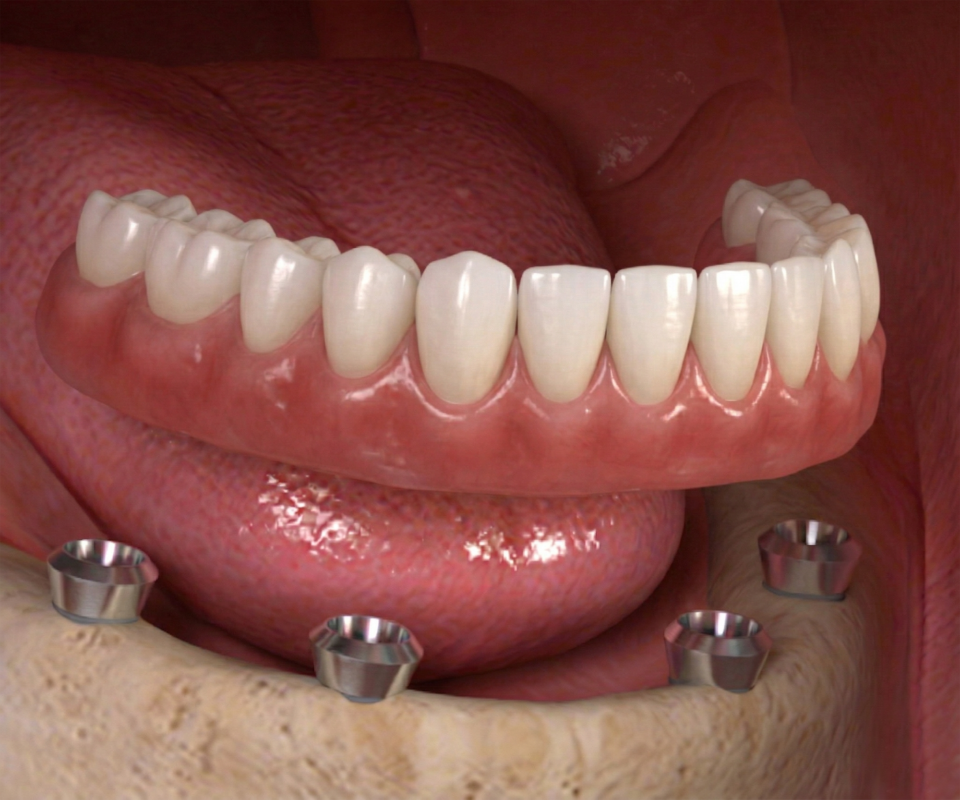

- Removable Implant Overdentures: Removable implant dentures are upgraded from traditional dentures designed to “snap” into place over special attachments using locators, balls, or bars to dental implant posts.

The first step is installing tooth implants is embedded the implant posts into the jaw bone. In this illustration, 4 implants are placed into the jaw bone. After implant placements, your dentist makes a re-check appointment about 5 to 7 days later to re-check the implant wound healing.

3. ATTACHING THE OVERDENTURES

During your return visit, your dentist takes a panoramic x-ray to check if the implant posts is successfully integrated with the jaw bone. Your dentists takes tooth impressions to construct your permanent dentures in the dental labs. On its delivery, locators, balls or bars are screwed into the implant posts with the dentures snapped over securely over.